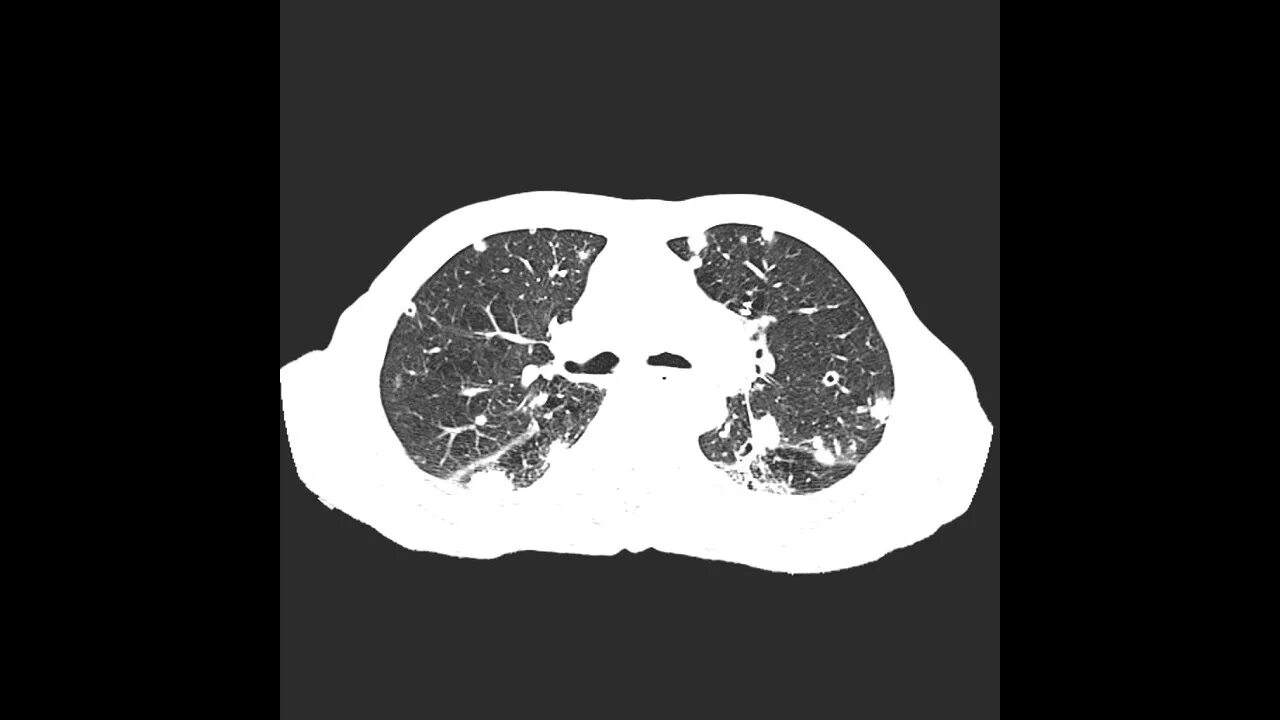

Метастазы в легких терапия